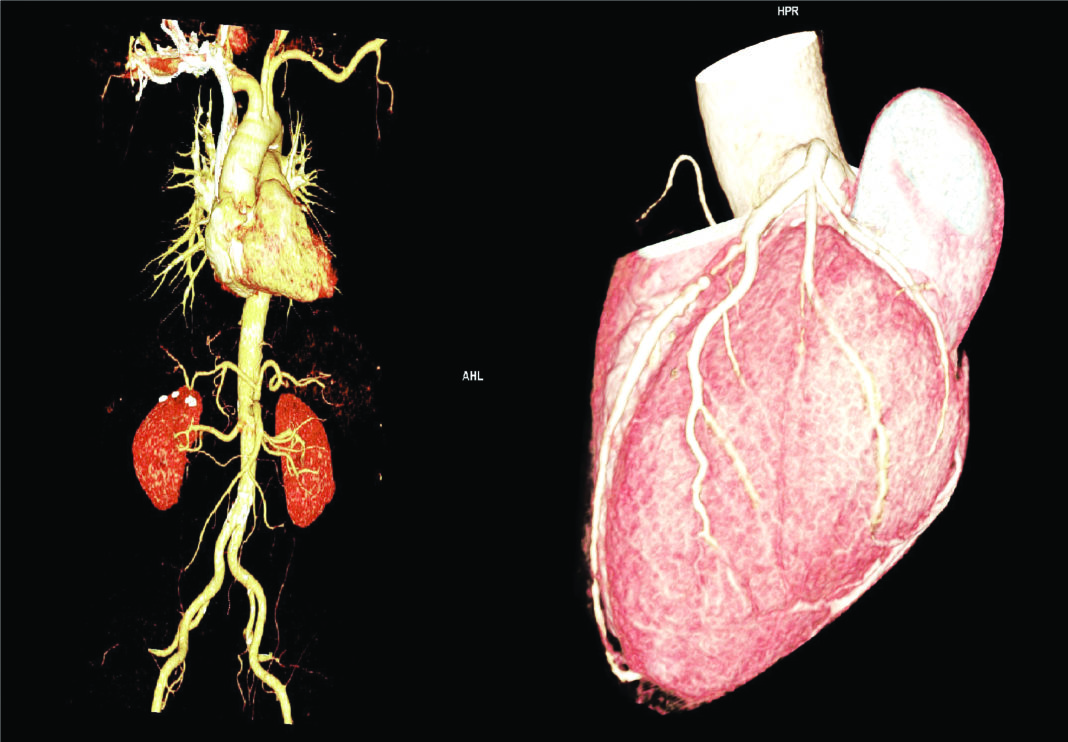

De curând, am achiziționat un aparat COMPUTER TOMOGRAF performant GO TOP 128 slice SIEMENS prin care, în premieră în Oltenia, realizăm examinări de înaltă rezoluție, inclusiv ANGIOGRAFIE CT.Investiția a venit în întâmpinarea nevoilor pregnante ale pacienților care efectuau aceste investigații în alte zone ale țării. Datorită achiziţiei rapide a imaginilor, cu inaltă rezoluţie, examinarea angiografică prin tomografie computerizată (angio-CT) are abilitatea de a oferi informaţii anatomice, fiziologice şi de caracterizare a vaselor în cateva secunde şi permite reconstrucţii 2D şi 3D în orice plan, facilitând un diagnostic rapid, noninvaziv, cu riscuri minime.

Angiografia CT este o investigație imagistică non-invazivă a vaselor care se efectuează pe aparate computer tomograf multislice de ultimă generație. Este utila în: evaluarea structurilor vasculare, evaluarea afecţiunilor neurovasculare, caracterizarea anevrismelor, stenozelor şi anomaliilor vasculare, analiza vascularizaţiei capului şi gâtului, incluzând arcul aortic şi emergenţa arterelor cervicale; planificarea tratamentului intervenţional, evidenţierea circulaţiei colaterale, starea parenchimului cerebral, excluderea disecţiei arteriale cranio-cervicale, evidenţierea şi evaluarea stenozelor vasculare, poate face diferenţierea între un tromb ocluziv total, subocluziv sau stenoza aterosclerotică – patologie trombo-stenotică. Există mai multe tipuri de angiografie, în functie de ce parte a corpului este investigată.

Angiografia coronariană / Coronarografia/ Cardio CT este singura procedură de diagnostic care permite verificarea cu exactitate a condiţiei arterelor coronare (vasele care alimentează inima) şi depistarea eventualelor îngustări (stenoze) care pot diminua sau stopa fluxul de sânge al muşchiului cardiac (ischemie) și să determine durere toracică (angina) sau infarct miocardic. Se pot detecta anomalii coronariene, evalua by-pass-urile, stenturile, aprecia morfologia și funcția valvelor cardiace, funcționalitatea miocardului și gradul de perfuzie al acestuia.

Angiografia renală – se verifică vasele de sânge care alimentează rinichii.Angiografie periferică – Angiografia CT a membrelor inferioare este o metodă imagistică foarte practică, neinvazivă, utilă în cazul pacienților cu afecțiuni cronice ale arterelor periferice, identificarea stenturilor vasculare, a trombozelor sau în cazul traumatismelor de la nivelul membrelor inferioare care implică structurile vasculare (lacerţiile arteriale, disecțiile, ocluziile trombotice, fistulele arterio-venoase), evaluarea extensiei bolii aterosclerotice la arterele membrelor inferioare, piciorul diabetic. Examinarea angio CT a membrelor inferioare ajută la identificarea plăcilor de aterom depuse pe pereții vaselor de sânge.